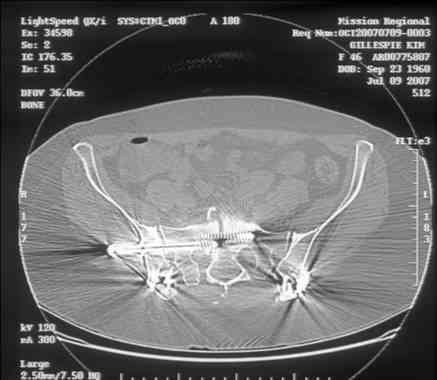

Re: Sacral Non-Union

Here is a magnified view. Sorry about the quality but the CT was scanned into our system.